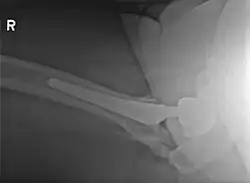

Elbow

• Incidence

• Isolated dislocation: 3-10%

• Dislocation + fracture: 15-20%

• Rush Univerisity; 2011 PMID 22016869 -- "Radiation therapy for heterotopic ossification prophylaxis afer high-risk elbow surgery." (Strauss JB, Am J Orthop (Belle Mead NJ). 2011 Aug;40(8):400-5.)

• Retrospective. 44 patients, status post surgery and single-fraction radiation, with NSAID use. Median follow up 4.5 months

• Outcome: radiographic evidence of HO in 48%, however in all cases small and not functionally significant. No complications

• Conclusion: RT in combination with NSAID is safe and efficacious